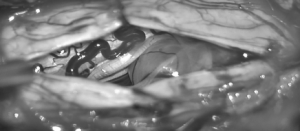

48-year-old Mr. Li came to Hong Kong from China to seek medical treatment for his paralyzed legs and fatigue symptoms. He has been receiving Chinese and Western therapies in China for two years, but his symptoms have not been improved. Two years ago, Mr. Li only felt pain in his feet, but slowly found that his feet were unstable and his thigh muscles were weak. At the same time, he gradually felt numbness in his legs and had difficulty lifting his legs when he walked quickly. Recently, it has also affected frequent urination. After detailed consultation and examination, it was found that Li’s symptoms were too unusual. It may be caused by a severe intervertebral disc compressing the Cauda Equina Syndrome, or a spinal tumor compressing the spinal cord and affecting the disease. The author immediately arranged an MRI scan of the spine, and it turned out that a 2cm Nerve Sheath Spinal Tumor had grown in the 9/10th spine of the thoracic spine, which had seriously compressed the spinal cord. He was immediately referred to a neurosurgeon on the same day to arrange admission for surgery to remove the tumor. On the second day after the operation, the patient felt that the weakness and paralysis of the feet were greatly improved.

Benign tumors in the spinal canal will not metastasize to other parts, and there will be no immediate life threatening, but because it grows in the spinal canal, when it is large, it will compress the spinal nerve and produce symptoms similar to sciatica. In severe cases, it will cause The lower limb paralyze and will not return to normal over time.